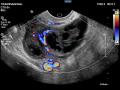

Tag: ultrassonografia transvaginal

Diagnóstico por imagem em ginecologia - Quinto ano medicina